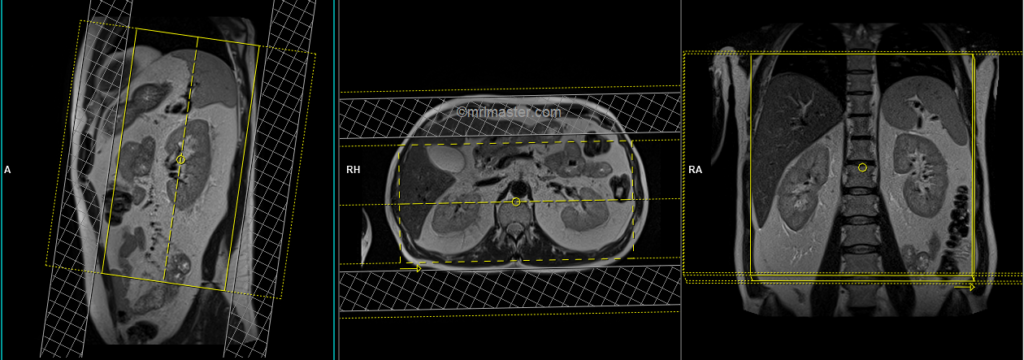

T1 VIBE DIXON 3mm axial BH pre GD(In-opposed phase and water sat)

Plan the axial slices on the coronal plane; angle the positioning block perpendicular to the thoracic vertebra. Check the positioning block in the other two planes. An appropriate angle must be given in the sagittal plane, perpendicular to the long axis of the kidney. Slices must be sufficient to cover both adrenals from the diaphragm down to the lower pole of the kidneys. Phase oversampling and, in the case of 3D blocks, slice oversampling must be used to avoid wrap-around artifacts. Using a saturation band on the top and bottom of the block will help to reduce artifacts from vascular pulsation and breathing. Instruct the patient to hold their breath during image acquisition.

When planning the axial breath-hold scans, it is crucial to utilize the breath-hold vibe coronal sequence. This is because during inhalation, the diaphragm exerts downward pressure on the liver, causing a shift in its position from the initial localizer scans. Therefore, to accurately capture the desired imaging area of the liver, it is important to account for this positional change by utilizing the breath-hold vibe coronal sequence.